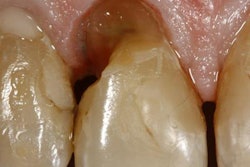

To aid the reincorporation of teeth with previous endodontic treatment, glass-fiber posts are inserted into the root canal. Debridement of the canal also is both mandatory and a major element of endodontic success, according to the authors.

The researchers studied the effect on the bonding strengths of glass-fiber posts with different surface treatments in post spaces roughened by an Er:YAG laser (Fotona Fidelis Plus III laser, Fotona). In addition, they looked at the bonding strengths of prefabricated glass-fiber posts exposed to surface treatments in teeth with excessive substance loss and also the effect of laser treatment of the root canal surface on bond strength.